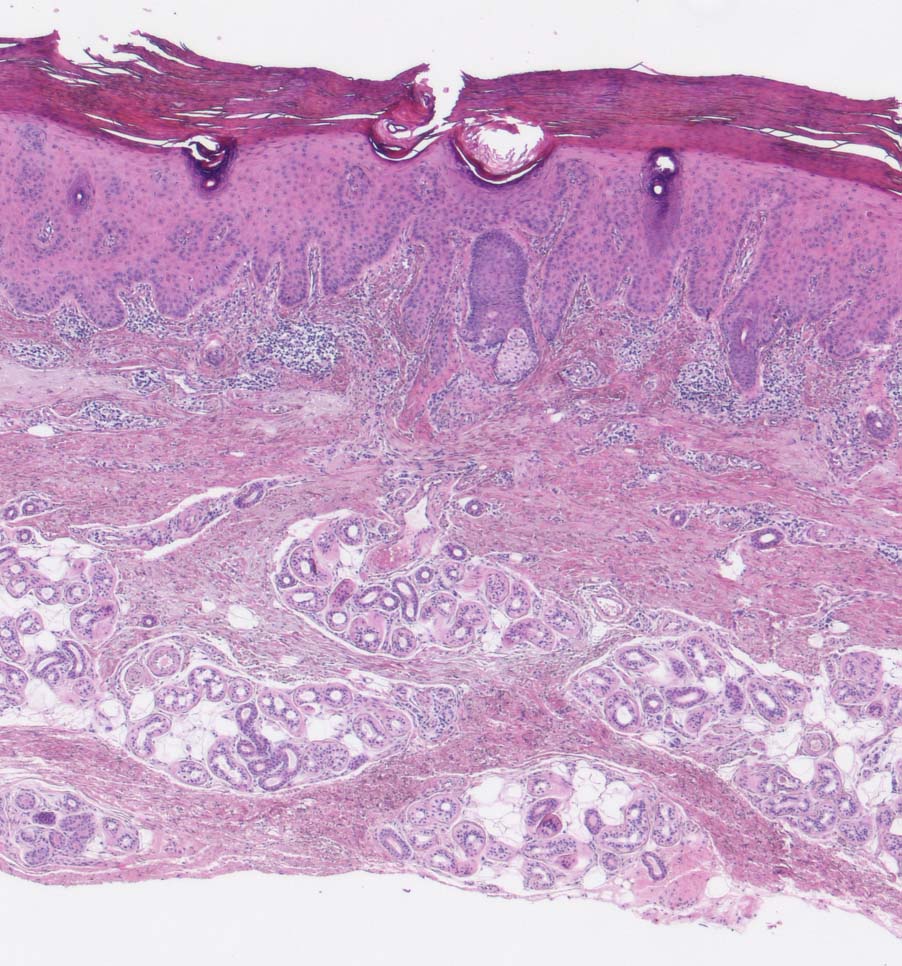

PathoPic – image database / PathoPic ID 9308 - Solare Präkanzerose (Keratose) hyperkeratotischer Typ

Solare Präkanzerose (Keratose) hyperkeratotischer Typ

Haut, Hand palmar, Finger

Hyper-parakeratotisch verhornende akanthotisch verbreiterte Epidermis. Abblassung des Plattenepithels und Dysplasie in den basalen Abschnitten der Epidermis. Deutliche solare Elastose der Dermis.

Histologie

25